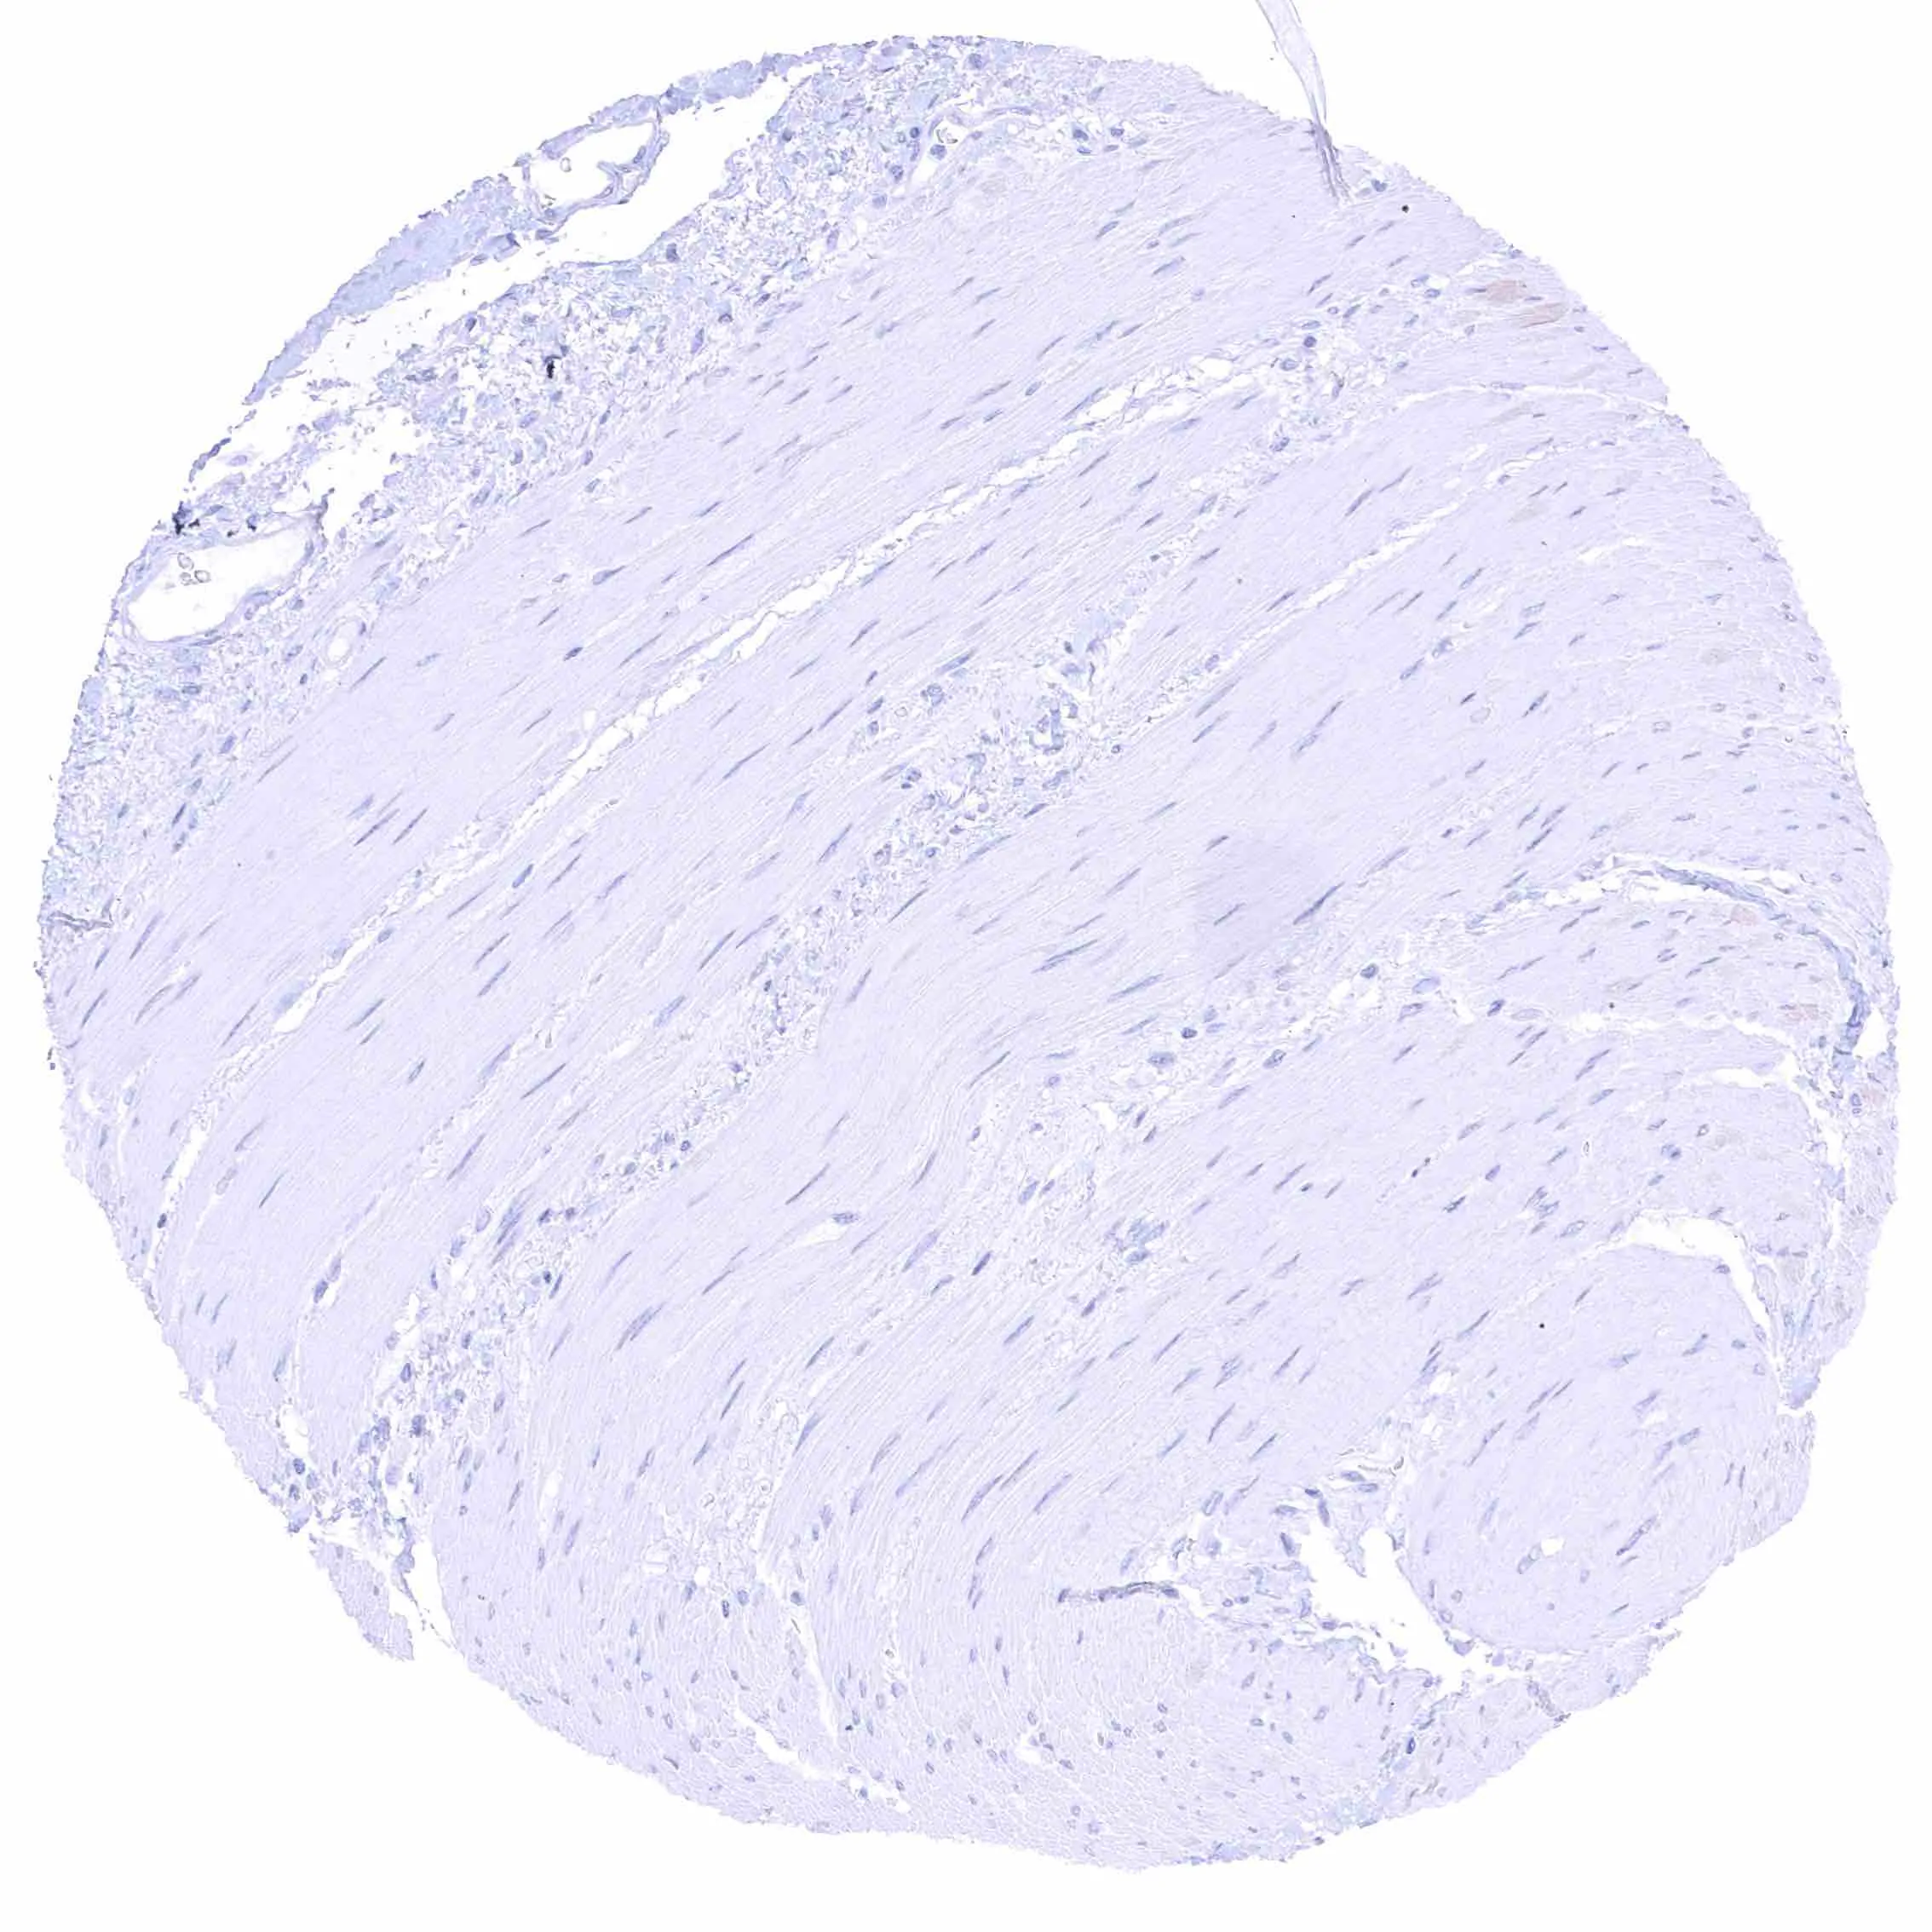

Uterus, myometrium – Distinct NPR-C staining of endothelial cells in some but not all blood vessels